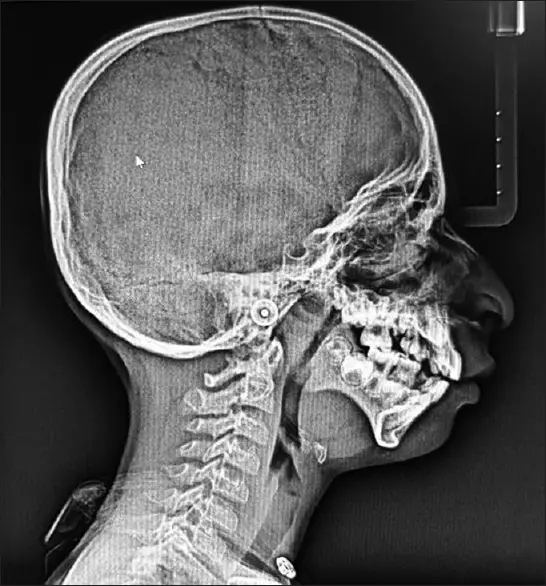

Belirgin antegonial çentiği gösteren lateral sefalogram (Kaynak: Datta Meghe Tıp Bilimleri Enstitüsü)

TCS öncelikle yüzdeki kemikleri ve dokuları etkileyerek az gelişmiş elmacık kemikleri, çene ve çene ile sonuçlanır. Sonuç olarak, etkilenen bireyler genellikle aşağı doğru çekik gözler, küçük ve biçimsiz kulaklar ve çökük bir çene ile karakterize edilen belirgin bir görünüme sahiptir.

Bir dizi muayene, konsültasyon ve genetik testten sonra, tıp uzmanları nihayet kesin bir teşhise ulaştılar - Treacher Collins sendromu (TCS). Nadir görülen bu genetik bozukluk, cenin gelişimi sırasında yüz kemiklerinin ve dokularının gelişimini etkileyerek yüz şekil bozukluklarına ve işitme bozukluklarına yol açar. TCOF1, POLR1C veya POLR1D genlerindeki mutasyonlardan kaynaklandığına inanılıyor, ancak bazı durumlarda neden tanımlanamıyor.